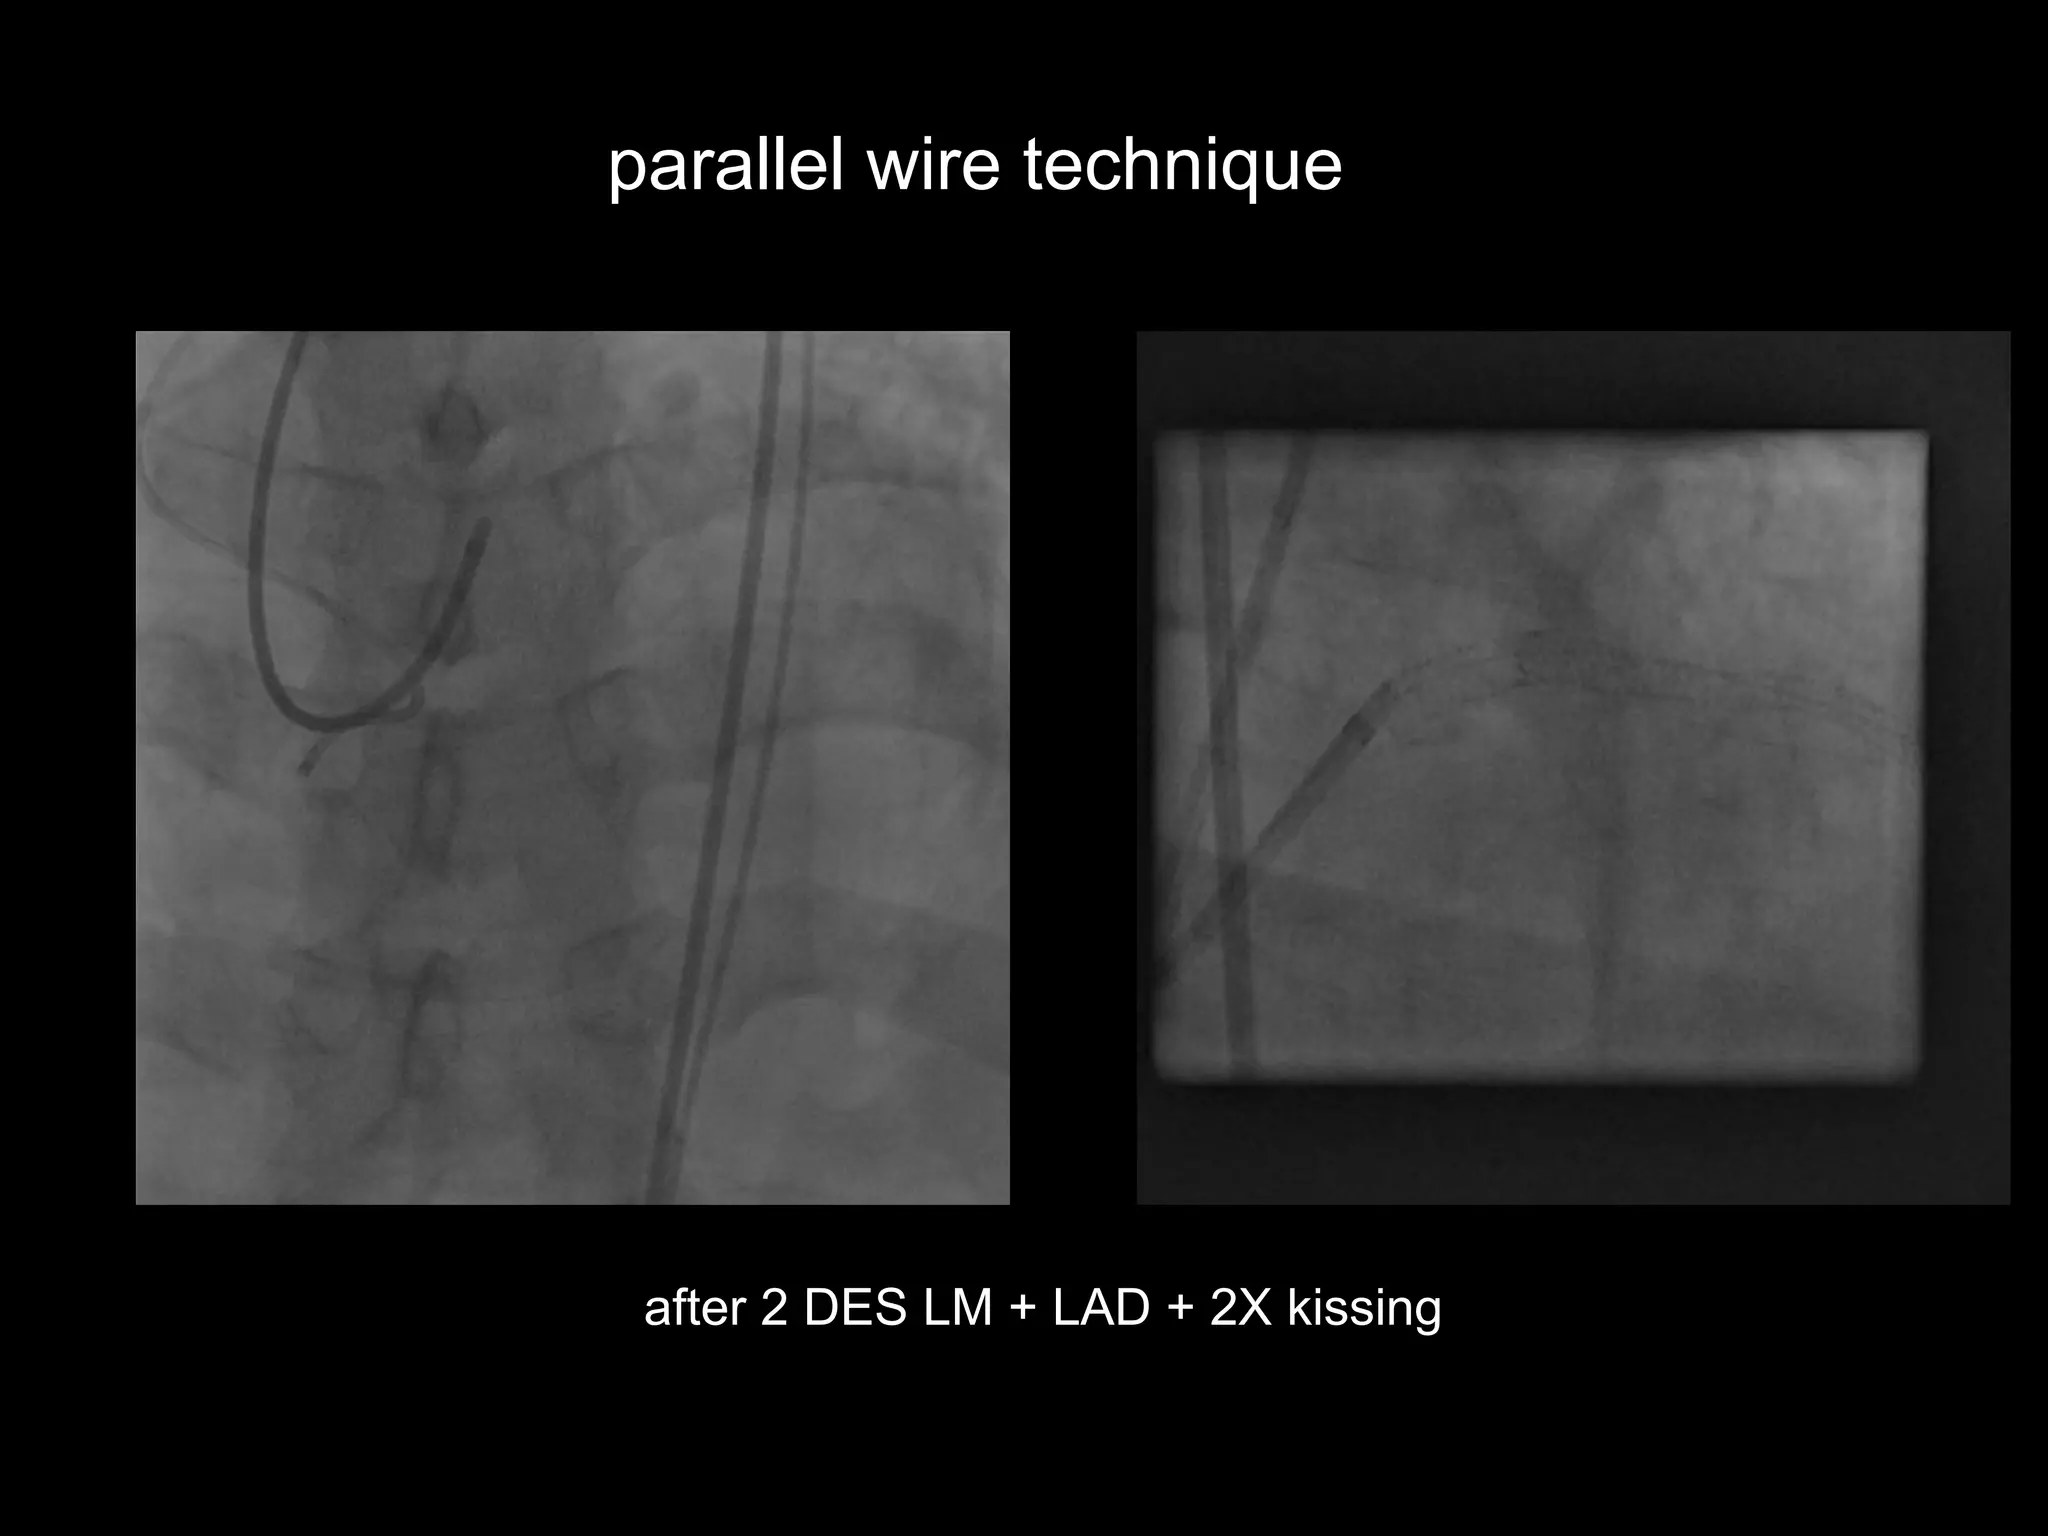

parallel wire technique

after 2 DES LM + LAD + 2X kissing